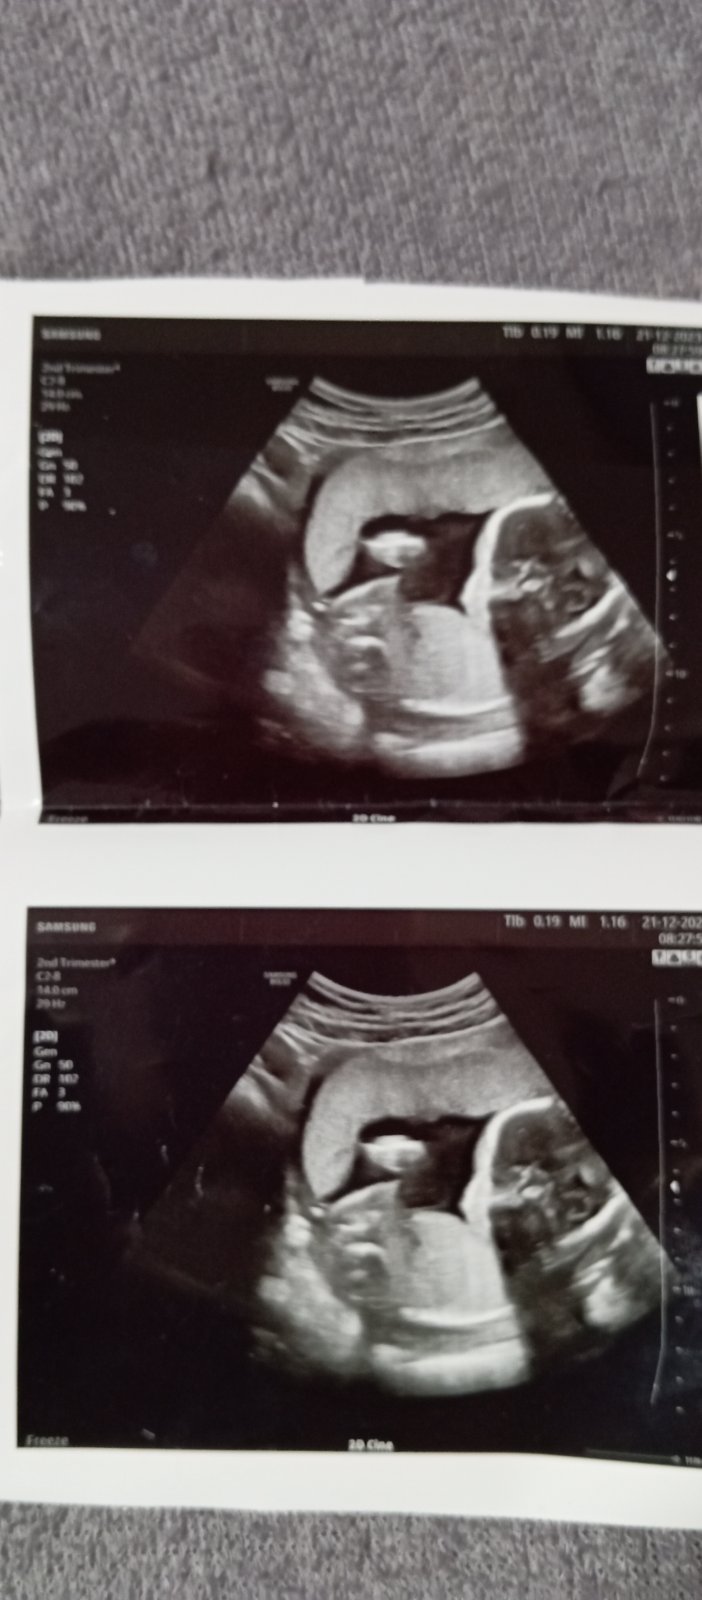

Můžete mi prosím poradit co to je za pohlaví miminka

Níže vidím kavové zrno…co řekl/a doktor/ka?

Nejde mi fotka přiblížit,ale vidím holku.. ☺️

Řekla bych že holčička

Tipují holcicku